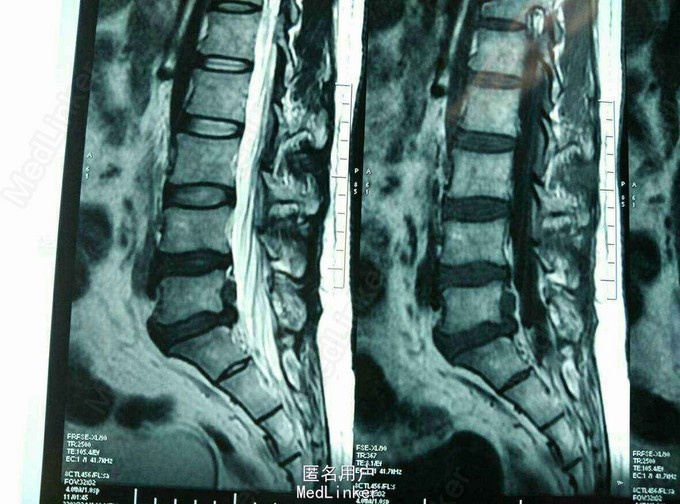

MRI及CT:L5S1 椎间盘脱出,向上游离。

诊断:L5S1椎间盘脱出(向上高度游离) 治疗:后路经椎板间入路椎间孔镜下髓核摘除,射频消融。